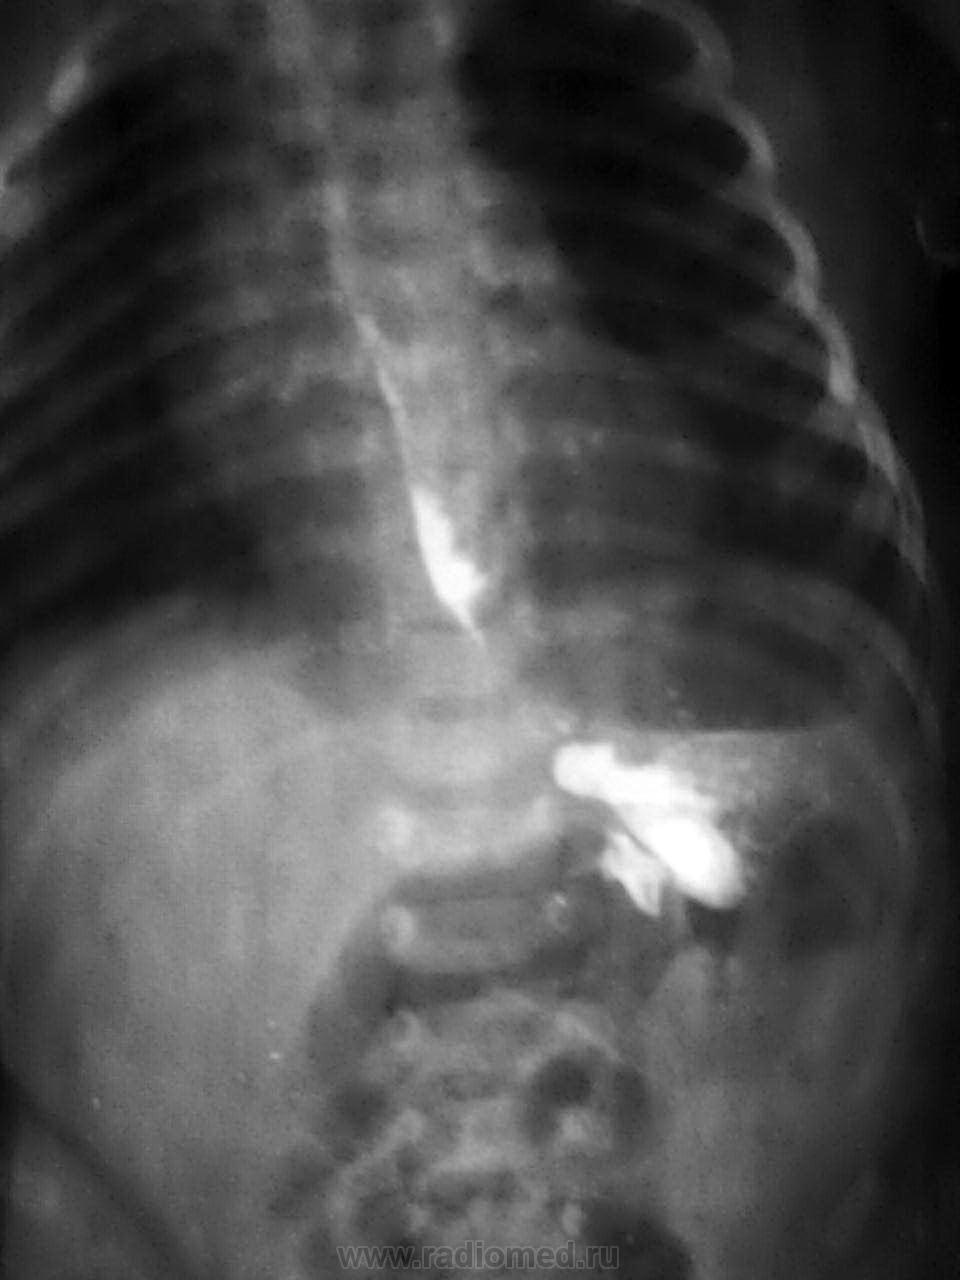

3 недели после рождения. Рвота после кормления.

-установили зонд

- подвесили

- контрастное вещество-барий

-динамика в течение 6 часов

-заключил:р-признаки ахалазии пищевода, пилоростеноза

Конечно, до месяца надо использовать только водорастворимый контраст. То есть через 6 часов барий еще в желудке, в кишечнике нет? Тогда, скорее всего, пилоростеноз.